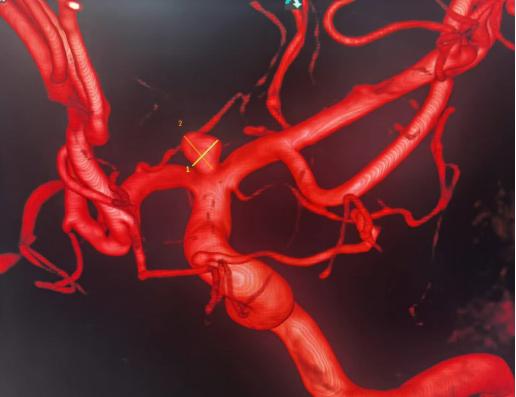

此次为一中年女性患者,以“头晕、头痛半月”之主诉来我院神经内科就诊,在完善了脑血管造影后,发现了该患者左侧大脑中动脉及大脑前动脉的分叉处有一大小约4.17×3.76mm大小的动脉瘤。由于该动脉瘤位置正对血流冲击位置,且有子囊形成,血压波动或者情绪波动等诱因都可能引发动脉瘤破裂出血,一旦出血可能危及生命。患者及家属十分忧虑,听闻我院神经外科脑血管亚专业组在脑动脉瘤的治疗方面有着丰富经验,遂转往我科继续治疗。

许刚副主任在仔细研究过患者的病历及影像资料后,建议患者早期行手术治疗,给出了患者三个治疗方案,开颅夹闭手术,常规弹簧圈加支架介入栓塞手术,而最后一种,则是目前最先进的方式WEB™植入术。经过详细告知和沟通,患者家属最终选择了行WEB™植入手术。于是在充分完善术前准备后,在影像介入室、麻醉科以及屈满莉护师的全力配合下,许刚副主任、张明副主任医师在全麻下为患者施行了大脑中动脉瘤内扰流装置WEB植入术,因为有之前的手术经验,手术过程十分顺利,仅用时15分钟就完成了WEB植入,术中即刻造影显示动脉瘤内造影剂滞留明显,其余左侧大脑中动脉、大脑前动脉等血管均通畅。患者术后顺利苏醒,拔管后未诉特殊不适,言语功能及肢体功能均未受影响。2天后患者出院。

术前动脉瘤影像